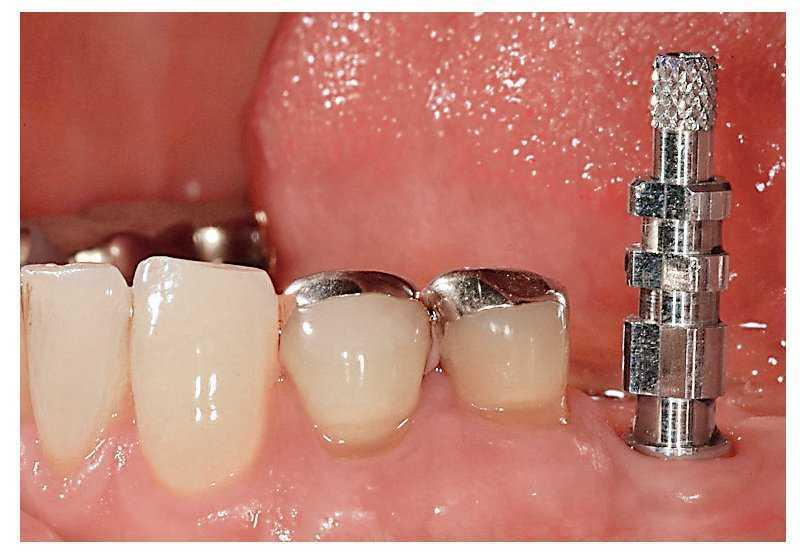

En el presente caso se orientó correctamente el implante en función de la sustancia ósea existente y de los dientes adyacentes, y en el maxilar opuesto se orientó bucolingualmente (fig. 5b). De este modo, los contornos y la función de la corona del implante se ajustan de forma óptima a lo largo del eje del implante y se evitan fuerzas laterales indeseadas4,18,52,57. Una representación tridimensional de la situación clínica, una planificación adecuada del tratamiento y una orientación correcta del implante facilitan la consecución de la meta protésica. Un implante insertado a la suficiente profundidad crea espacio para un pilar con recorrido subgingival del margen y un perfil de emergencia de la corona satisfactorio (fig. 5c).

Fig. 5b. Vista desde oclusal: el implante con cofia de cicatrización.

Fig. 5c. Vista desde oclusal: el implante sin cofia de cicatrización. La posición del implante extremadamente favorable en relación con el diente adyacente, así como el tejido blando periimplantar sano, posibilitan una toma de impresión limpia.

La impresión de los implantes pueden realizarse optativamente en cubeta abierta o cerrada. La impresión en cubeta abierta es preferible en virtud de su mayor exactitud, especialmente cuando se debe tomar la impresión de varios implantes. Una orientación mesiodistal y bucolingual correcta (fig. 5d) posibilita una configuración óptima del pilar, independientemente de si la corona está cementada o atornillada (figs. 5e a 5g).